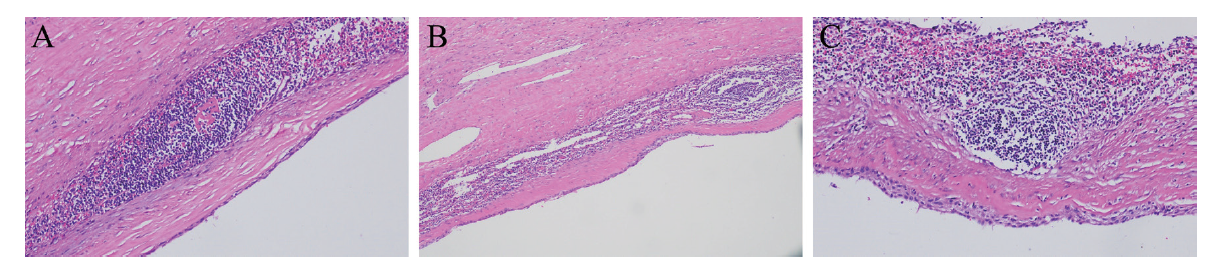

1个月后患者返院复查腹部MRI,胰腺尾部见类圆形T1WI低信号影,T2WI高信号影,DWI呈稍高信号,内壁光滑,增强扫描未见强化,考虑胰腺尾部囊性占位,良性病变以假性囊肿可能性大(图3)。患者为进一步治疗,入住我院肝胆外科,有手术指征并与患者及家属沟通后于全身麻醉下行腹腔镜胰体尾切除术+脾切除术+腹腔粘连松解,术中见胰尾处有一大小7.0 cm×8.0 cm的囊性肿物,包膜完整,质韧,活动度可,肿物与脾动静脉、主胰管间距约0.5 cm以上,其余胰腺部分质地软,胰腺周围、脾动脉淋巴结及脾门淋巴结部分未见肿大。术后病理结果:囊壁由纤维组织构成,内壁大部分区域未见被覆上皮,局部被覆鳞状上皮,囊壁内见较多淋巴细胞浸润,局部淋巴滤泡形成(图4)。最后诊断为PLEC。

图4 一例PLEC患者病理组织切片(HE染色,×100)

注:A为囊壁由纤维组织构成;B为内壁大部分区域未见被覆上皮;C为局部被覆鳞状上皮,囊壁内见较多淋巴细胞浸润,局部淋巴滤泡形成。